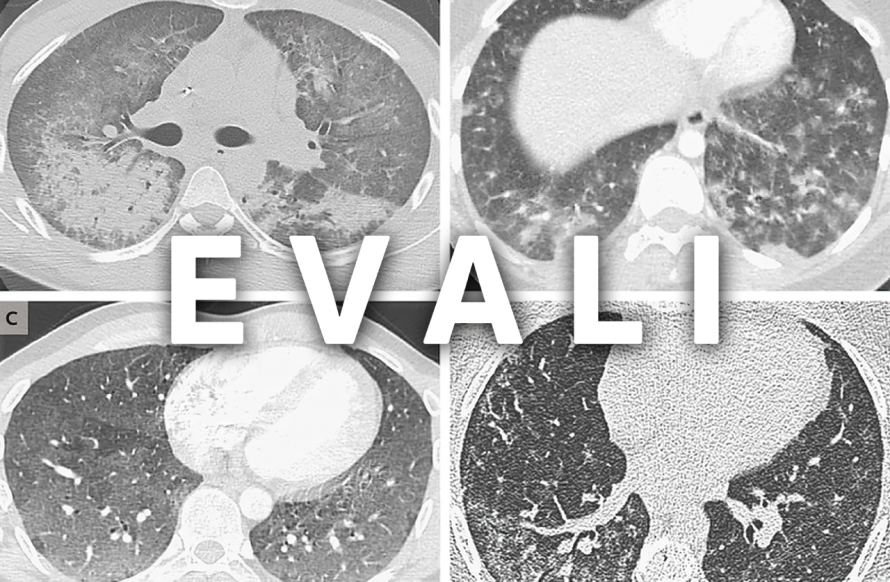

Офіційних критеріїв немає. Лікар запитує про вейпінг протягом останніх 90 днів і проводить обстеження, як при пневмонії: аналізи крові, рентген або КТ грудної клітки, пульсоксиметрію, виключення COVID-19 та грипу.